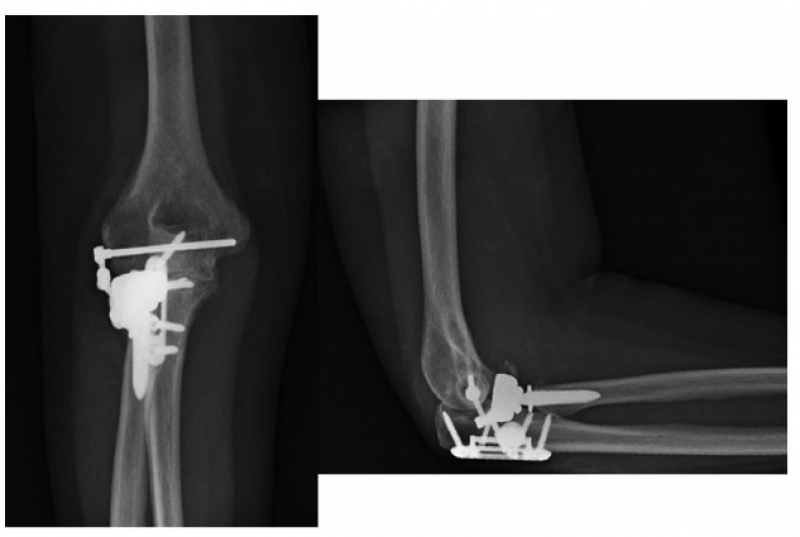

1、肘关节旋转轴三维定位

国内蒋协远教授团队在世界上率先采用三维导航机器人进行肘关节旋转中心定位。TiRobot机器人导航辅助肘关节旋转中心轴定位能够极大地降低主观判断造成的旋转轴偏移,提高轴心定位精准度,减少反复透视验证的过度辐射及反复调整轴心导针的骨质破坏,避免可能的血管、神经损伤,显著减小降低术后肘关节活动阻力,并减少外固定针松动、断裂及外固定架断裂等并发症的发生率,从而整体提高治疗效果。